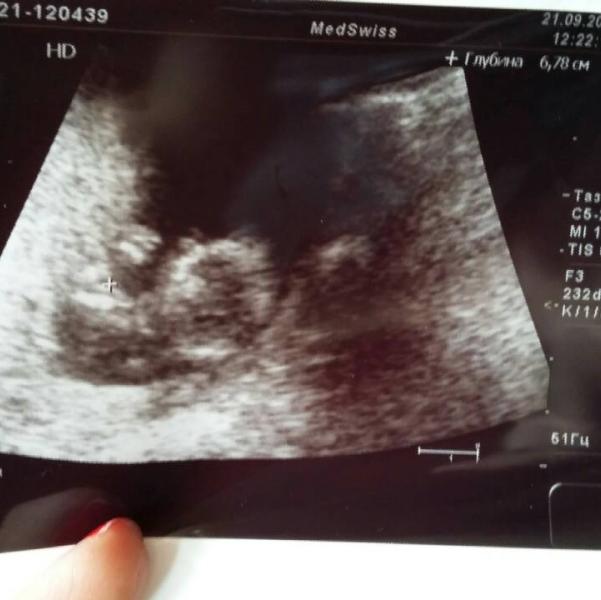

доброе утро, красотки!✌ давайте о приятном) Вы же наверняка помните свое первое знакомство с малышом на первом скрининге?😊 что вам запомнилось больше всего⁉ мой малыш (пока еще толком не понятно какого пола😄) повторял за мной движения рук, представляете???))) было так забавно.А сасосинаяале узи я легла положив одну руку кистью ко лбу, он лежал так же, но мы особо с врачом не придали этому значение,а потом когда пригласили супруга посмотреть, я поменяла положение рук и опустив левую руку, приложи...